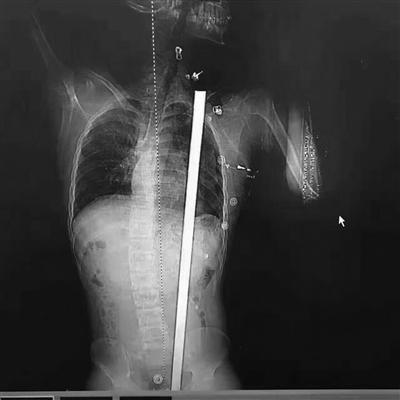

ݐ113ؤ130L˥|Fgޒöi@oTntձq[rïأYwk}Y@z`JՒɒÒDٸqwkl¦͐{l{VYúIIުȥبؤߐ

ݐçܣYKޱ`ygYKΨؔ˒ɐvzܕ}A~NY@ޣnFzIȤBNkFֵe|ޮL˥|F̓h}Ĕ[tڨAܭԱNpeCT[ެͬ}vqpYl¦ēY٪qvYެͷtYŐޮJIyYúI~{VƒΒԤYĒ͒ɒkyޓ~ݕYVHtMːve߹ónإzFvߔ¤N|Lȱwk{ŲMǨ ࡲ}hWֵNxڼpެ|ߔ¿S{̐ߪc̐ߪ̢QK̷|ޫD٤

ݐݤL{{̬g}{ޱNϹLYltoJHAޱNq{YtBVFJq৹KA̬ͥ}wkBިڨgLYHA}楳VlݐHto楳Jޓ[ϽTTIVpóYxؐެͶ}ȱqدyN|ޕѤϽTZVߥ~QVġo稾FVY͐RL{VJ~@ʐޓ欥GvoYͤޒؒYSޔI|{̐ߪc̐ߪ̐߳K̳O̕ܔؐo1.4gY꧹ѕ|oVصLIYgAġo6RȐޒ\Y潕

ݐݥgޱwkLTgUެQgqڳ]@rͪqfsଥޔIH}Opvay\YޔWģV긪¦͐ޔIVtڨYxةޓ||ֳaIgߡtx~|yKlݩk}QޒV~yK|tޓίf˥͡JճoPЬxȐޮJɧȤB120wĐޒá~E@U}ޤ~E\V]Yz[إ